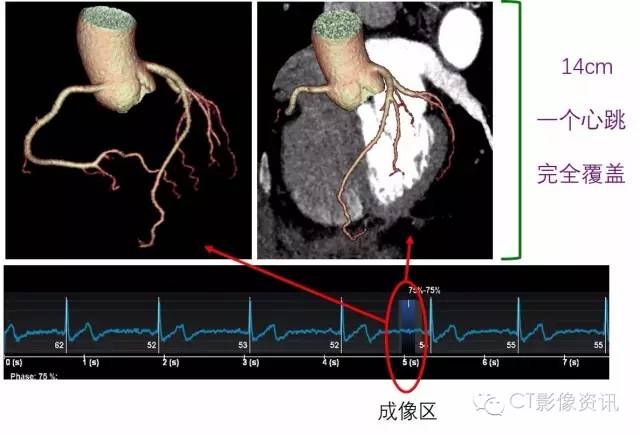

武汉大学人民医院于11月刚装机的世界顶级CT—Revolution CT实现了影像同仁十多年的夙愿!最大16cm宽度探测器的超大体型能够一次曝光就覆盖完成11~14cm的心脏范围;业界最好的29ms 3D时间分辨率可以像抓拍百米冲刺的运动员那样冻结住极度不规则心律的心脏!高超过硬的技术含量,让所有的冠脉CTA都在一个心跳之中完成!您知道这意味着什么吗!就在您刚要一吸气的时候,您的冠脉CTA已经检查完了!连屏气都省啦!

接下来我们一起探秘Revolution CT的超高技术One Beat的心脏解决方案!带大家一起看看One Beat技术是如何的轻松弹指一挥间解决各种顽皮跳动的、每个人都不可再重复的各种心率/心律的冠脉CTA。那靠的可是硬本领!0.28s转速+16cm探测器宽度才能办到的。

16cm的探测器覆盖完整心脏

同样的这样的检查在探测器宽度不够宽的设备上需要多个心跳才能完成。而每多一个心跳的曝光,就意味着更多的辐射剂量,现在咱们的Revolution CT可以直接像做体检一样进行!One Beat不再是一个目标,是每天常规进行的检查!